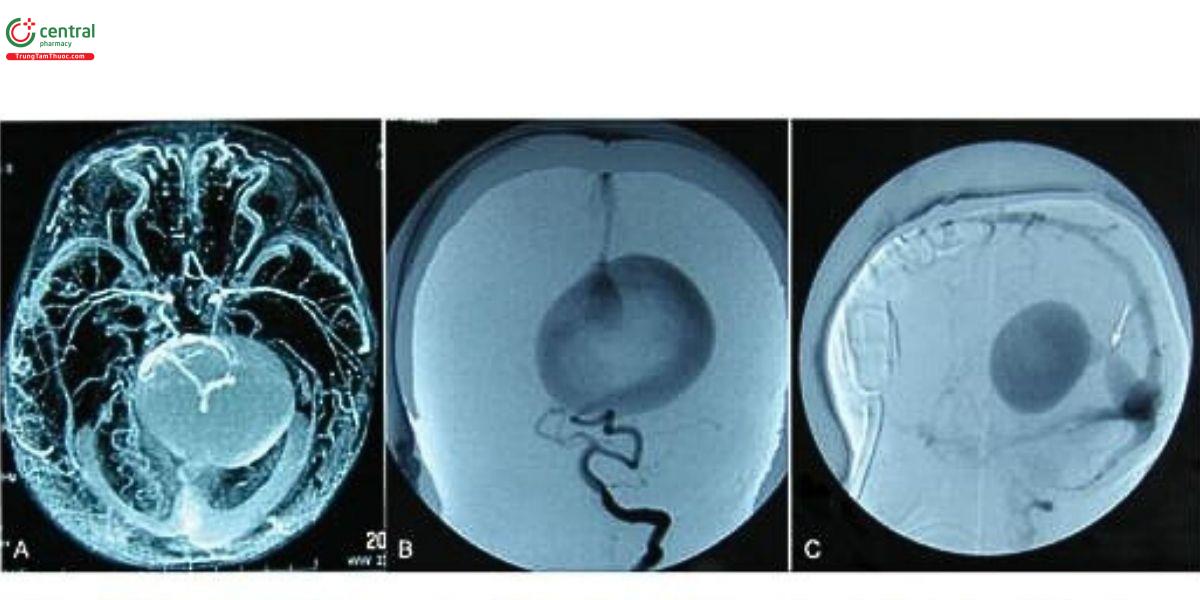

8 Điều trị nội mạch

Trường hợp đầu tiên được điều trị bằng nút mạch được Davis báo cáo vào năm 1950. Với sự phát triển của điều trị nội mạch, tỷ lệ tử vong đã giảm từ 60-82% xuống còn 11%. Mục tiêu của điều trị nội mạch là giảm dòng rò nội sọ hoặc thậm chí bịt tắc tất cả các lỗ rò (Hình 7). Thực tế, việc bịt tắc hoàn toàn không cần thiết, vì giảm khoảng một phần ba đến một nửa dòng rò là đủ để cải thiện các triệu chứng lâm sảng. Gần đây, một phân tích gộp cho thấy các biến chứng chính của điều trị nội mạch bao gồm thùng mạch não, chảy máu, thiều máu não, não úng thủy và thiều màu chỉ dưới. Việc phòng ngừa biến chứng phụ thuộc vào kỹ thuật nút mạch siêu chọn lọc đúng cách, lựa chọn vật liệu nút mạch và kỹ thuật chính xác, cũng như bảo tồn dẫn lưu tĩnh mạch não sâu bình thường. Ngoài ra, sự tồn tại của dẫn lưu bình thường giữa hệ tĩnh mạch sâu và VGAM cần được xem xét trước khi nút mạch để tránh các tác động bất lợi lên mạch máu não bình thường sau khi điều trị nội mạch. Mặc dù khó quan sát qua chụp mạch hoặc hình ảnh không xâm lấn, có thể do các yếu tố kỹ thuật và huyết động, dẫn lưu bình thường vẫn là yếu tố quan trọng trong kế hoạch điều trị.

Có hai phương pháp nút mạch, bao gồm đường động mạch và đường tĩnh mạch, trong đó đường động mạch được ưu tiên. Đường động mạch rồn có thể được sử dụng để nút mạch trong giai đoạn sơ sinh sớm, và động mạch đùi là lựa chọn thay thế khi động mạch rồn không khả dụng. Đối với đường tĩnh mạch, vẫn còn tranh cãi về kết quả của nút mạch đường tĩnh mạch. Trong các tài liệu trước đây, phương pháp này được coi là không khả thi do tăng biến chứng. Tuy nhiên, trong nghiên cứu gần đây, Orlov và cộng sự cho rằng đây là một phương pháp cứu vẫn an toàn và hiệu quả cho VGAM khí tiếp cận đường động mạch bị hạn chế. Ngoài ra, Meila và cộng sự mô tả một phương pháp kết hợp đường tĩnh mạch và động mạch, gọi là kỹ thuật "kissing microcatheter". Phương pháp này được xem là an toàn, với tỷ lệ biến chứng thấp và cải thiện kết quả tổng thể, đặc biệt ở trẻ sơ sinh có suy tim sung huyết. Các vật liệu nút mạch bao gồm cuộn coil, microballoon, N-butyl-cyanoacrylate (NBCA), Dung dịch Onyx, và copolymer ethylene vinyl alcohol. Ở loại đảm rối mạch mạc của VGAM, Onyx được khuyến nghị nhờ ưu điểm bịt tắc chắc chắn và ổn định hơn. Ở loại thành mạch, NBCA là vật liệu nút mạch được ưa chuộng do đặc tỉnh kết tủa nhanh và bám dính vào mạch. Ngoài ra, Joo và công sự lần đầu tiên báo cáo một bệnh nhân VGAM loại thành mạch được điều trị thành công bằng hệ thống Micro Vascular Plug, đây có thể là một lựa chọn tiểm năng

Phương pháp nút mạch theo giai đoạn được khuyến nghị để giảm thiểu các biến chứng. Khoảng thời gian giữa các giai đoạn thưởng là 3-6 tháng. Có một hệ thống phân loại điểm mới để quyết định điều trị được Mortazavi và cộng sự đề xuất, kết hợp các mạch nuôi động mạch với các triệu chứng lâm sảng và độ tuổi (Bảng 3). Nút mạch không khẩn cấp, và một lần nút mạch được khuyến nghị cho bệnh nhân có điểm 0-1. Nút mạch khẩn cấp và nhiều giai đoạn điều trị được đề xuất khi điểm là 2. Nút mạch theo nhiều giai đoạn hoặc điều trị giảm nhẹ được khuyến nghị cho bệnh nhân có điểm 3.